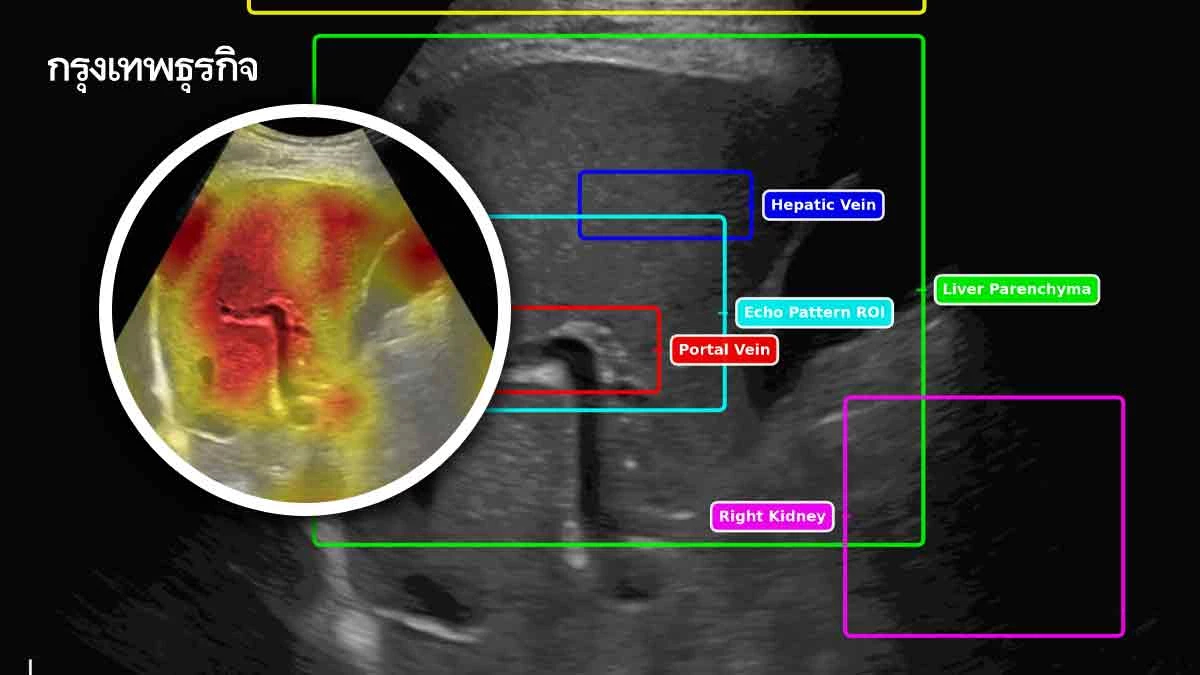

SmartLiva ทำงานเหมือน “อัปเกรด”จากภาพอัลตราซาวด์ขาวดำธรรมดาให้กลายเป็นผลวินิจฉัยที่อ่านง่ายและแม่นยำ โดยแพทย์อัปโหลดภาพผ่านเว็บได้ทั้งบนคอมพิวเตอร์หรือแท็บเล็ต จากนั้นระบบจะช่วยปรับภาพให้ชัดขึ้น คัดเฉพาะบริเวณเนื้อตับที่ต้องวิเคราะห์ และทำให้ภาพดูเข้าใจง่ายขึ้นด้วยการไฮไลต์เป็นสี(เช่น ตับเป็นสีแดง ไขมันเป็นสีเหลือง) เพื่อให้เห็นความผิดปกติได้ทันที

โดย AI จะทำการประเมิน 3 เรื่องพร้อมกันคือประเมินระดับพังผืด/ความแข็งของตับ (F0-F4),ตรวจหาความผิดปกติของเนื้อเยื่ออย่างถุงน้ำหรือมะเร็งตับ และตรวจหาพยาธิใบไม้ตับซึ่งตัวAIจะทำการประมวลวิเคราะห์และสรุปผลออกมาเป็นรายงานพร้อมภาพประกอบและคำอธิบายที่คนทั่วไปเข้าใจได้โดย AI ทั้งหมดถูกฝึกฝน (Train)ด้วยฐานข้อมูลภาพอัลตราซาวด์กว่า 50,000 ภาพ